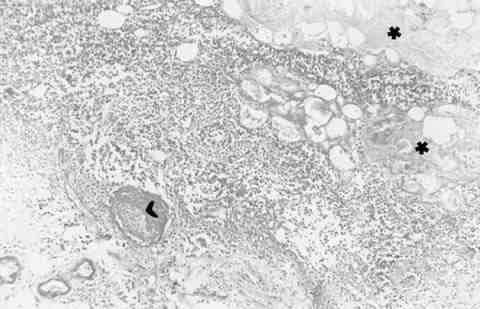

Figura 6

ÁREA DE NECROSIS ISQUÉMICA MASIVA (*) SECUNDARIA A TROMBOSIS (>), CON MARCADO INFILTRADO INFLAMATORIO (LINFOCITOS Y POLIMORFONUCLEARES). TINCIÓN DE P.A.S. (MAGNIFICACIÓN ORIGINAL X 50).